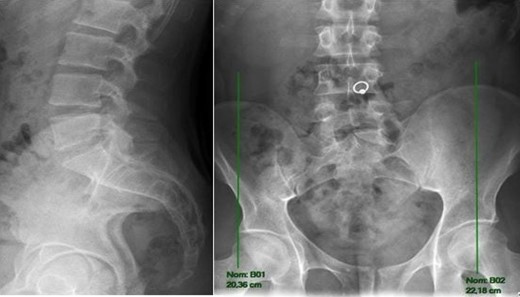

Radiography of the spine revealed an asymmetry of pelvis (Fig. 1), and despite a report refuting Baastrup’s disease, we can see a contact between spinous processes of L5 and S1 in extension (Fig. 2).

Radiography of lumbar spine in anterior-posterior and lateral views showing asymmetry of pelvis.